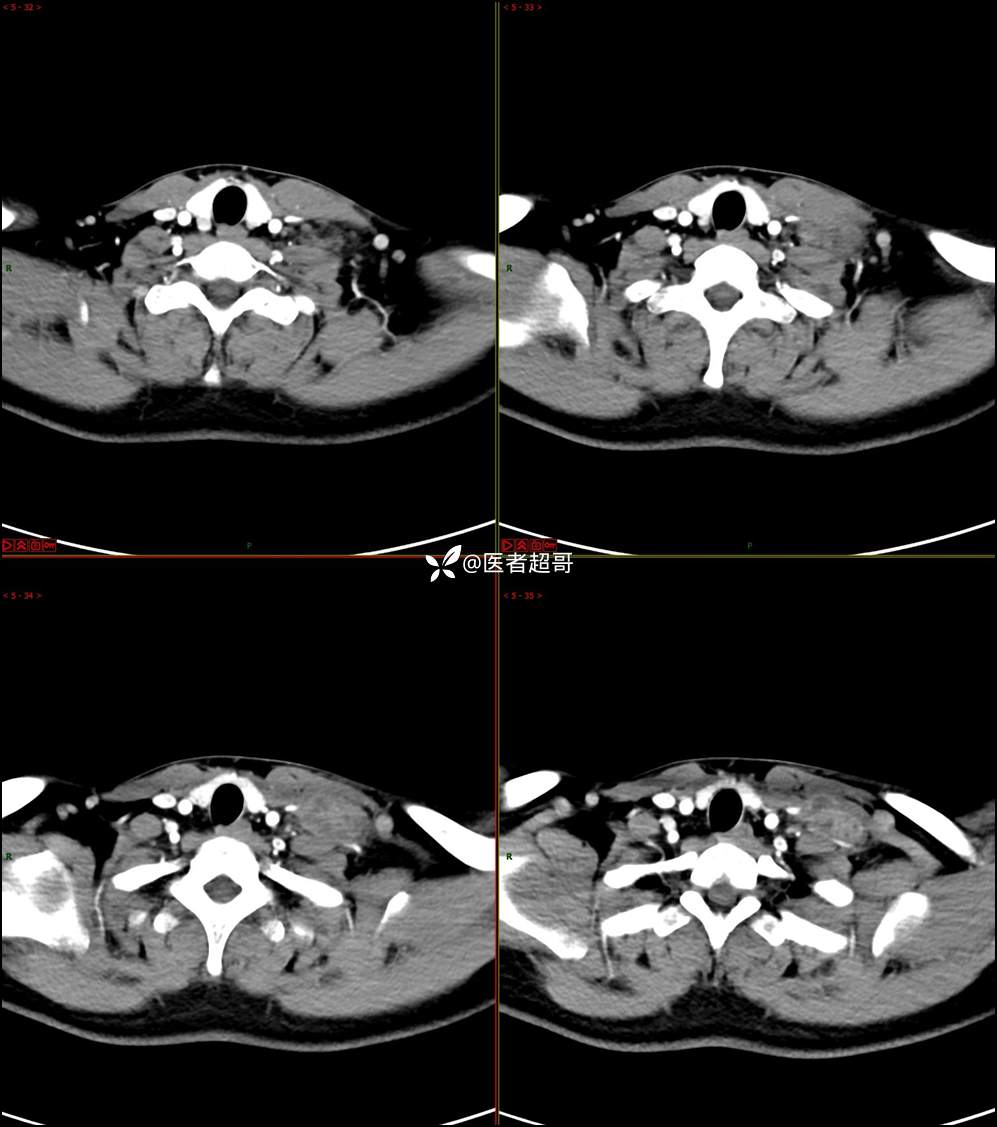

现病史:患者自述10余天前无意中发现左侧颈部一肿物,颈部活动时、进食时伴疼痛,无发热,患者前往人民医院就诊,给予输液治疗(头孢呋辛钠2g bid 硫酸阿米卡星0.4g qd、)10天,患者感肿物轻微变小,后患者为求进一步治疗,昨日来我院门诊就诊,给予颈部彩超示:左颈部实性肿物,神经来源?,左颈部肿大淋巴结;颈部ct平扫+强化示:左侧锁骨上区占位,神经鞘瘤?双侧颈部多发淋巴结;门诊以“局部肿物”收治入院,患者自患病以来,神志清,精神可,饮食睡眠可,体重无明显变化,二便正常。